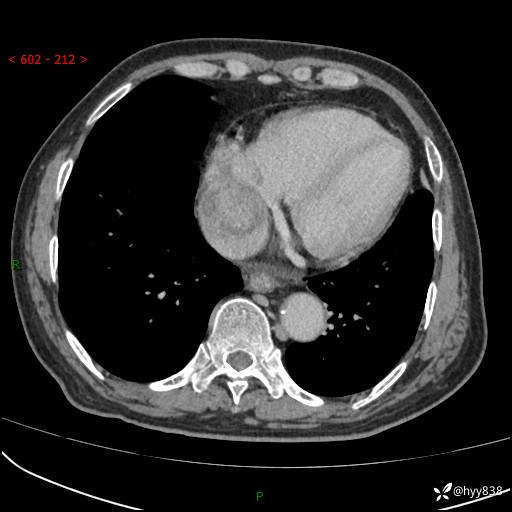

主诉:检查发现心脏肿物1周余。

现病史:患者一周余前因腹胀就诊我院消化科门诊,查心脏彩超提示右房内异常回声(粘液瘤?),无明显心慌、气喘、胸闷,无明显胸痛、咳嗽咳痰等不适,活动量增加后出现心慌、气喘不适。现为求进一步治疗,就诊我科,门诊遂以“心脏肿物”收入院。 自发病以来,精神睡眠一般,食欲尚可,大小便正常,体力下降,体重无明显变化。

胸部CT平扫+增强